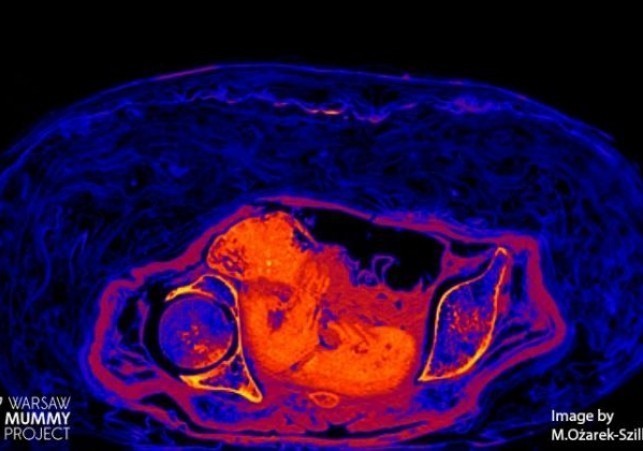

Płód w mumii egipskiej zachowany dzięki nietypowemu procesowi rozkładu

Płód znajdujący się w zmumifikowanej Egipcjance sprzed ponad dwóch tysięcy lat przetrwał do naszych czasów za sprawą bardzo nietypowego procesu rozkładu.… Czytaj więcej